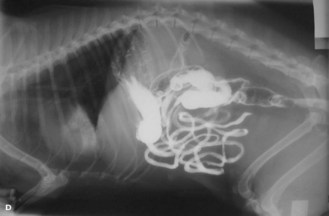

Procedure: Use of barium in the examination of the alimentary tract (Fig. 6. 21):

Figure 6.21 Use of barium to highlight the alimentary tract. Barium is visible in the stomach, the small intestine and has begun to reach the colon and rectum – taken 6.5 hours after administration.

6. Action: If you are performing a barium series (i.e. several radiographs taken at intervals) to follow the barium through the alimentary tract, give approximately 5 ml/kg of liquid barium (Fig. 6.21).

Rationale: A large volume is needed to prevent dilution as it passes down the tract.